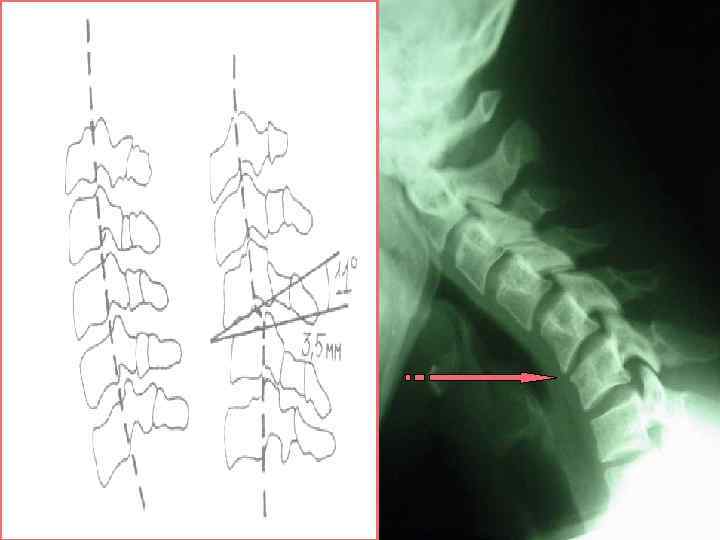

Спондилолиз Спондилолистез

Спондилолистез